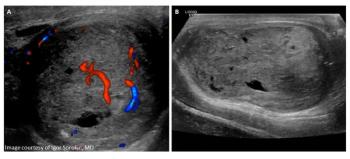

A 21-year-old male presented to the emergency department for evaluation of testicular pain and swelling 5 days after being struck in the groin.